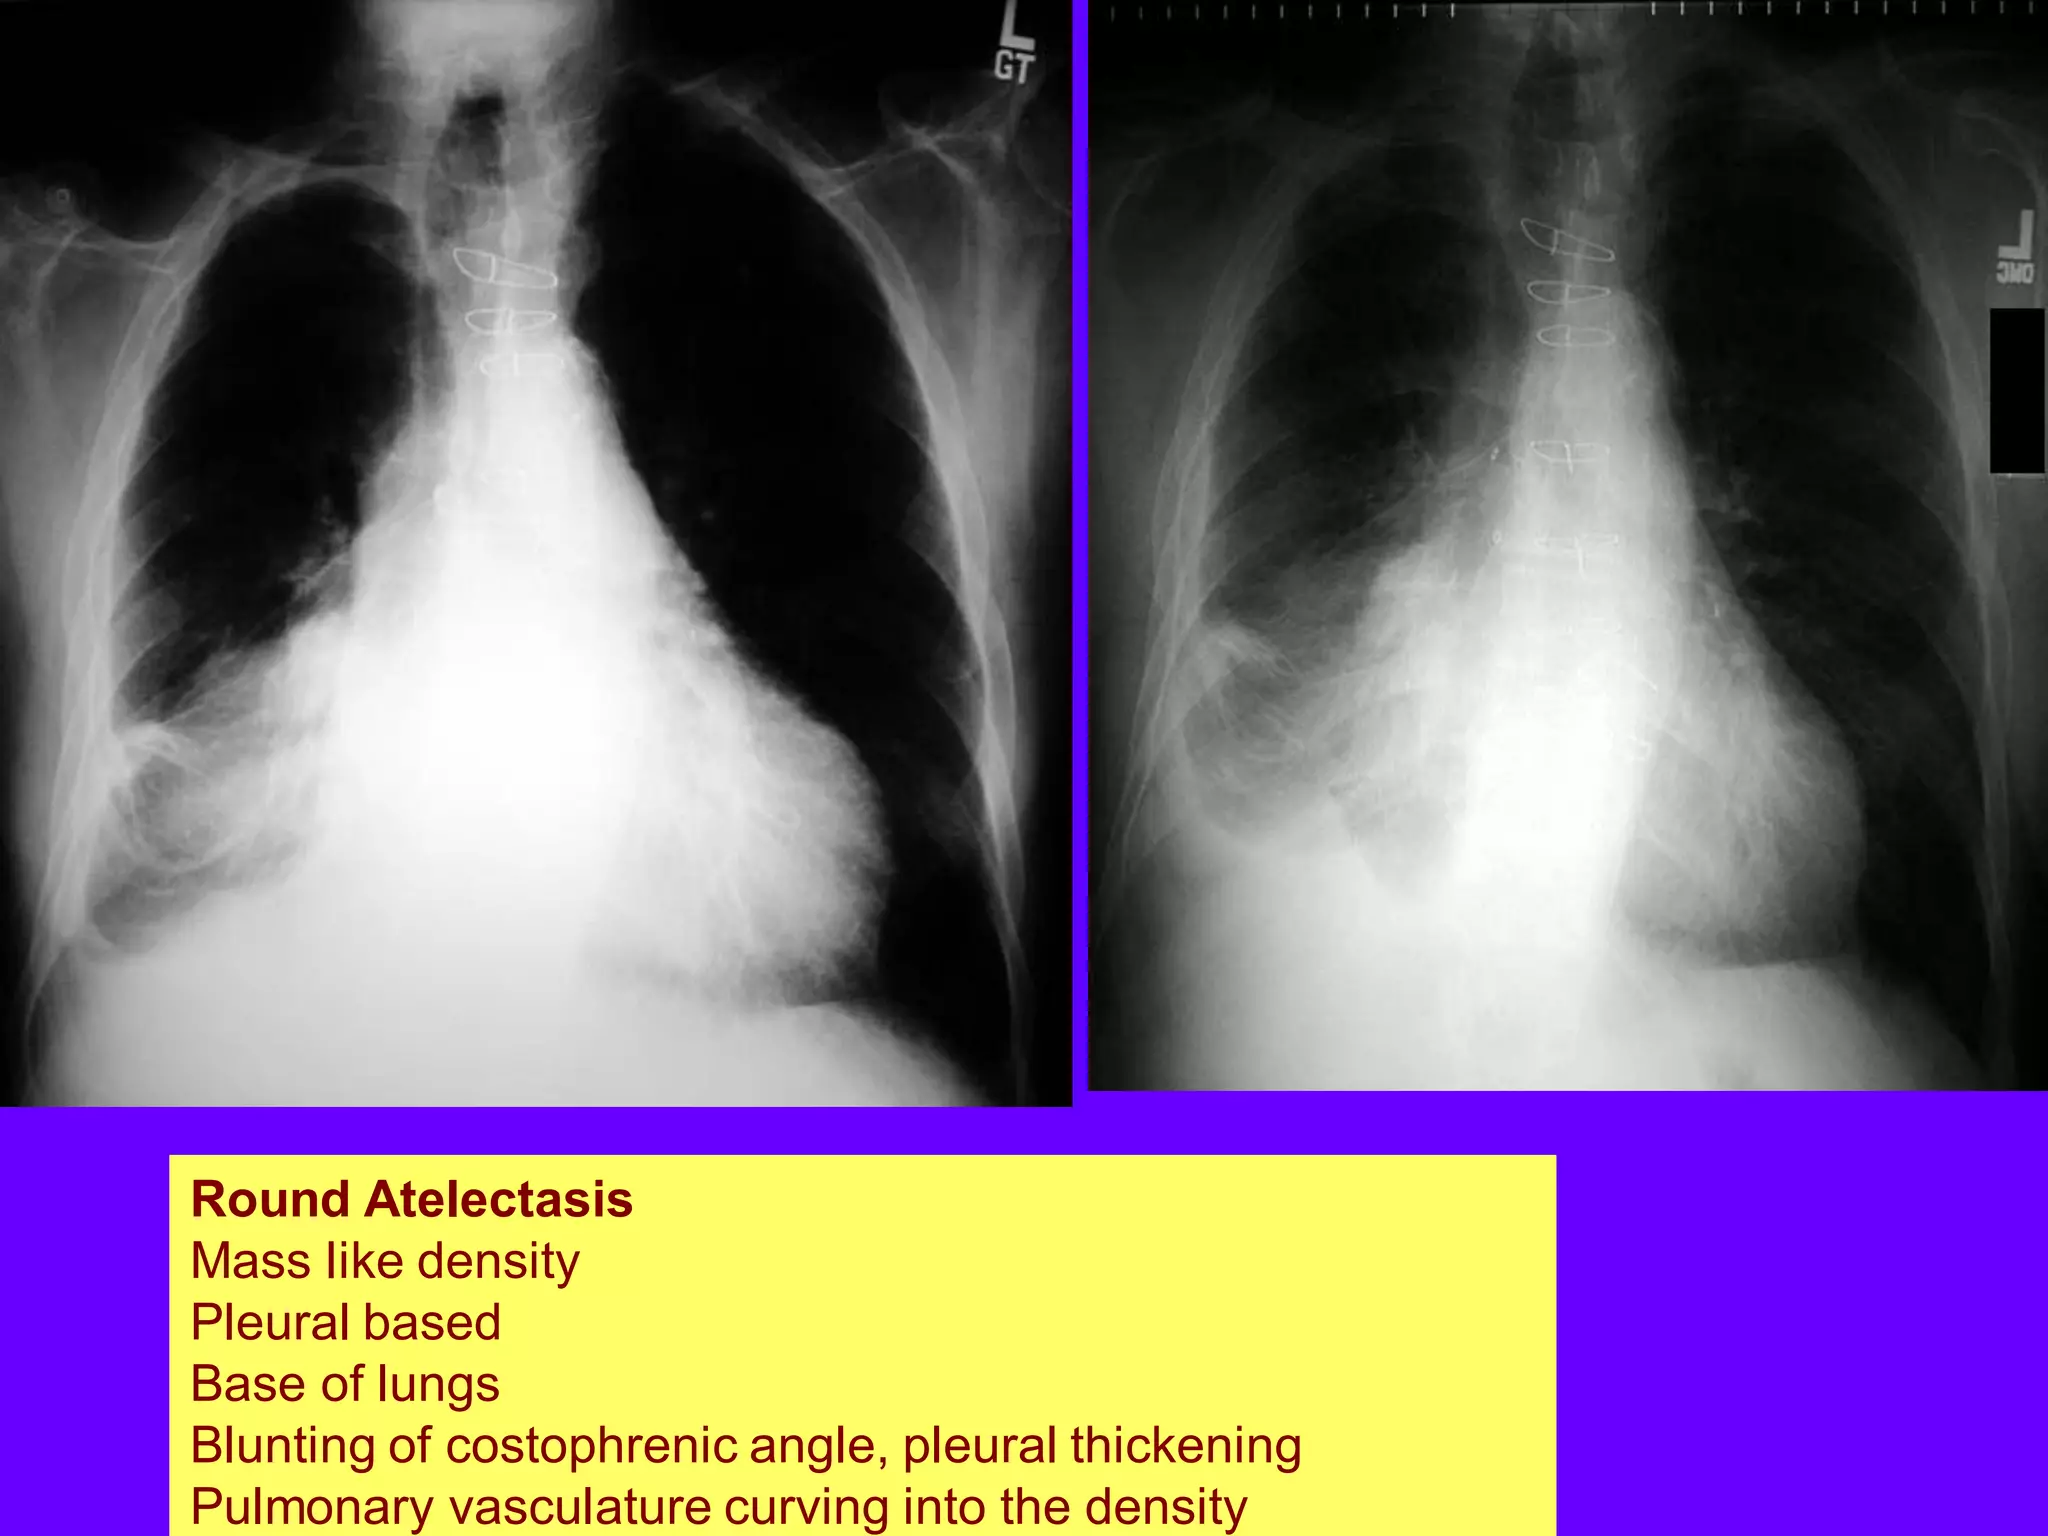

5-Round Atelectasis

An instance where the lung gets trapped by

pleural disease and is devoid of air.

Classically encountered in asbestosis.

Round Atelectasis

Mass like density

Pleural based

Base of lungs

Blunting of costophrenic angle

Pleural thickening

Pulmonary vasculature curving

into the density

Blunting of costophrenic angle, pleural thickening

Pulmonary vasculature curving into the density